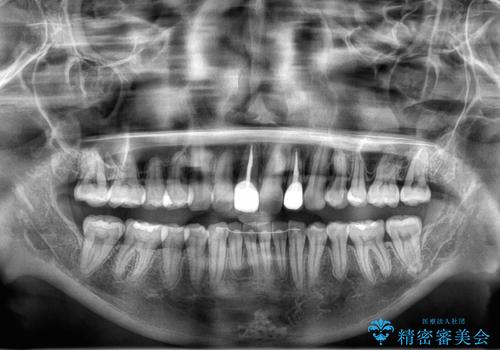

右下1が歯肉退縮していたため、アーチを拡げないように歯と歯の間を削って隙間をあけて並べています。